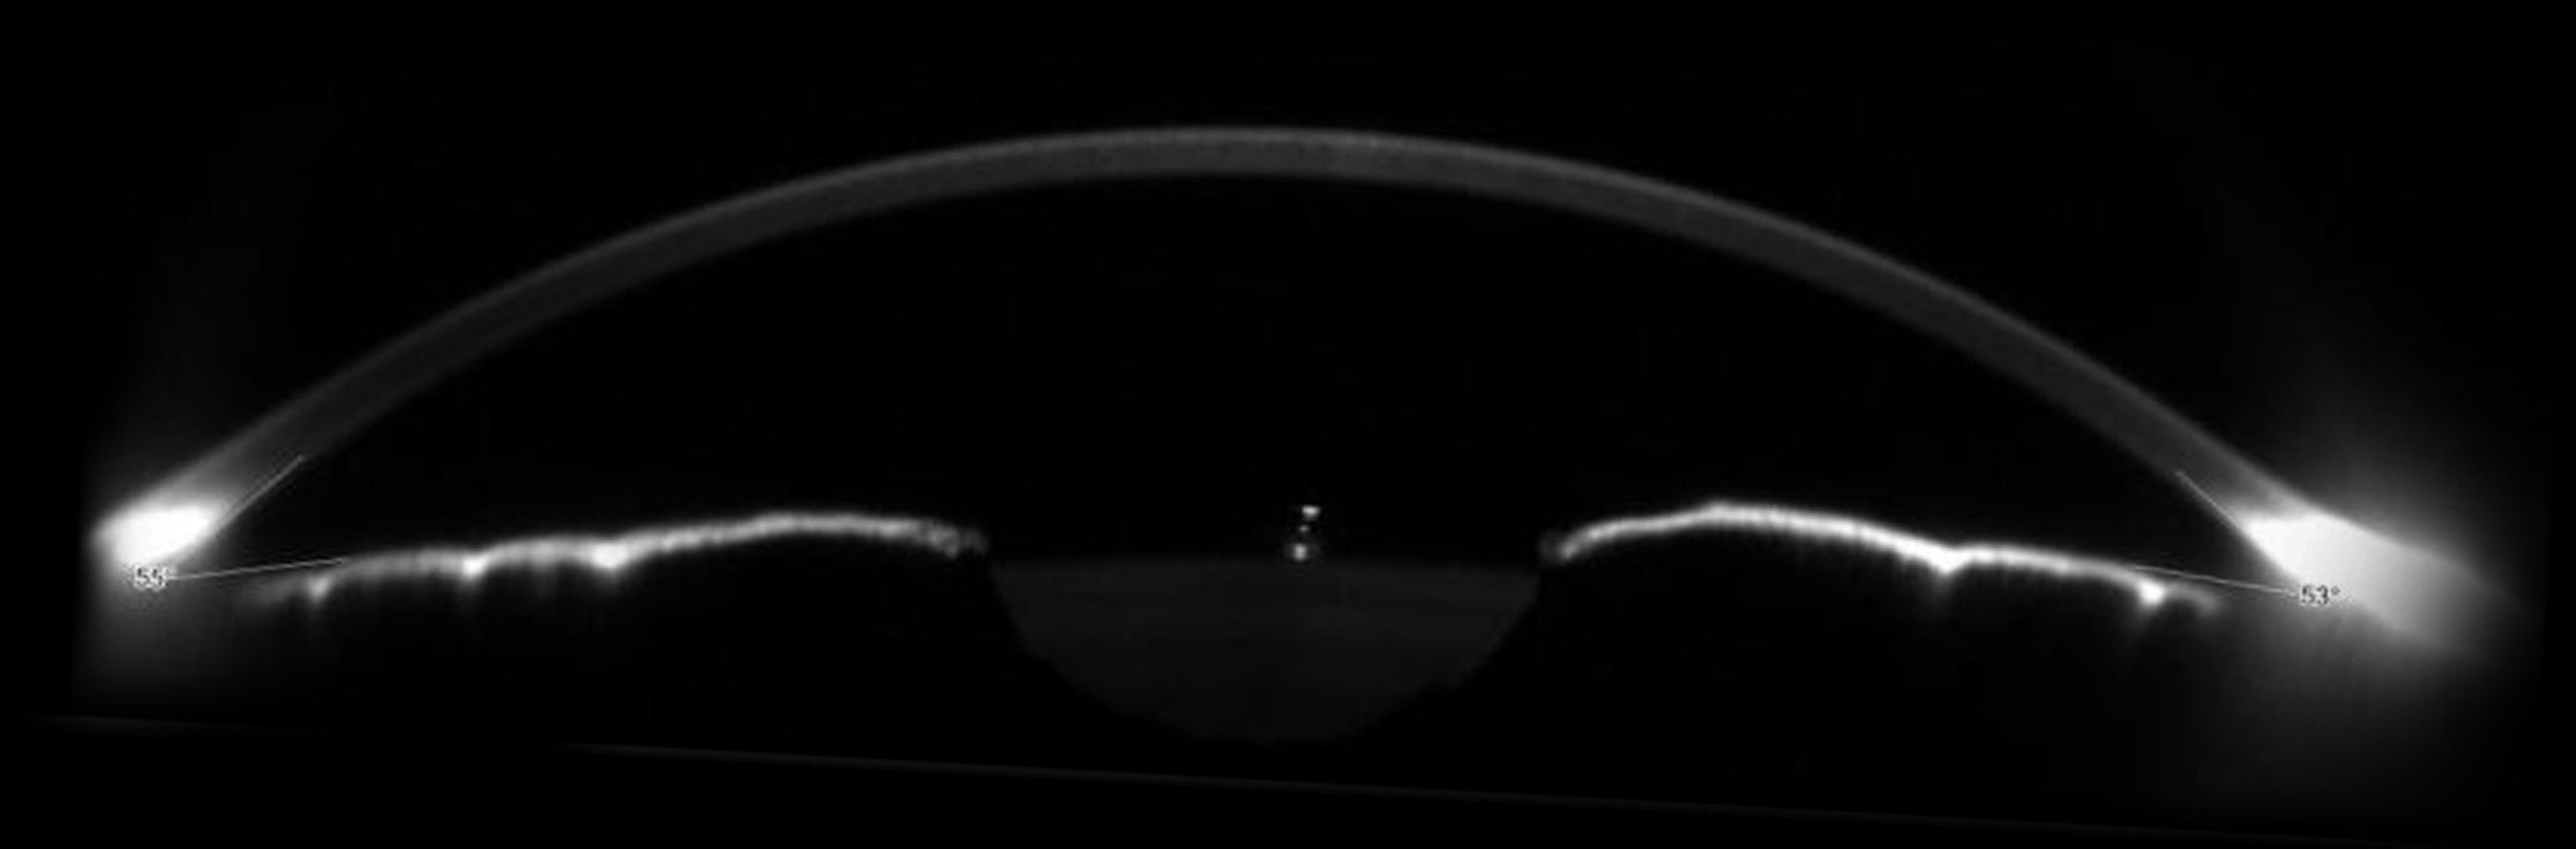

GLAUCOMA SCREENING

For glaucoma specialists Sirius+ enables the measurement of irido-corneal angles and pachymetry. These two values are useful in the diagnosis of the disease.